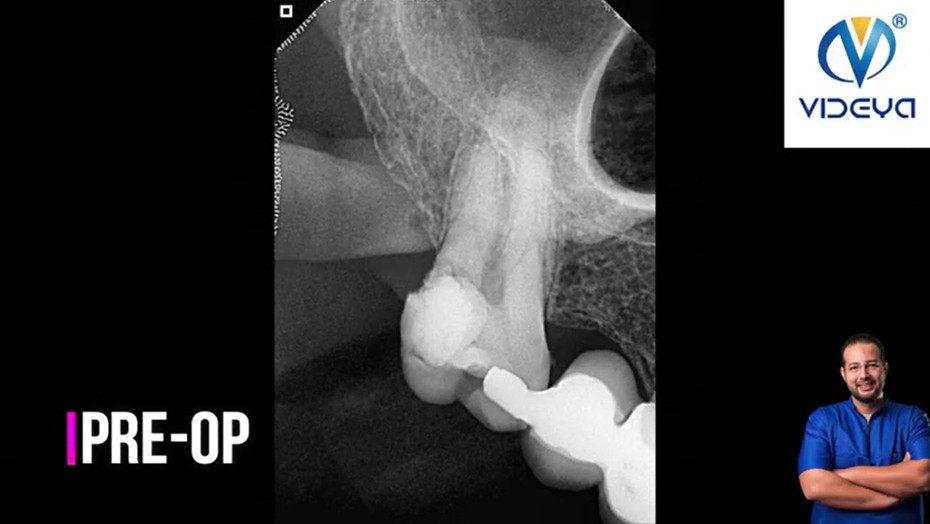

Gingivectomy + RCT of Lower 2nd Premolar